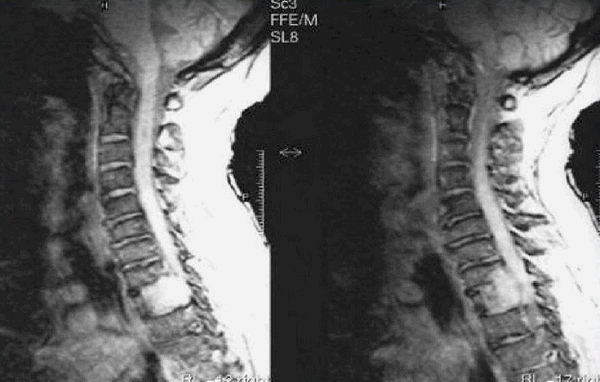

Снимки МРТ мягких тканей шеи

Проведение магнитнорезонансной томографии с использованием различных режимов повышает информативность исследования рыхлых элементов. Изучение особенностей кровоснабжения зоны интереса и диагностика новообразований требуют применения контрастного раствора. В качестве «окрашивающего» препарата используют хелаты гадолиния.

При увеличении железы в размерах по описанию томограмм можно определить характер гиперплазии. Узелки и капсулы выглядят на снимках МРТ как очаги с гипо- или гиперинтенсивным сигналом, отличным от реакции окружающих тканей. Метод показывает сдавление трахеи новообразованием, распространение патологического процесса в загрудинное пространство.

Исследование щитовидной железы на закрытом томографе